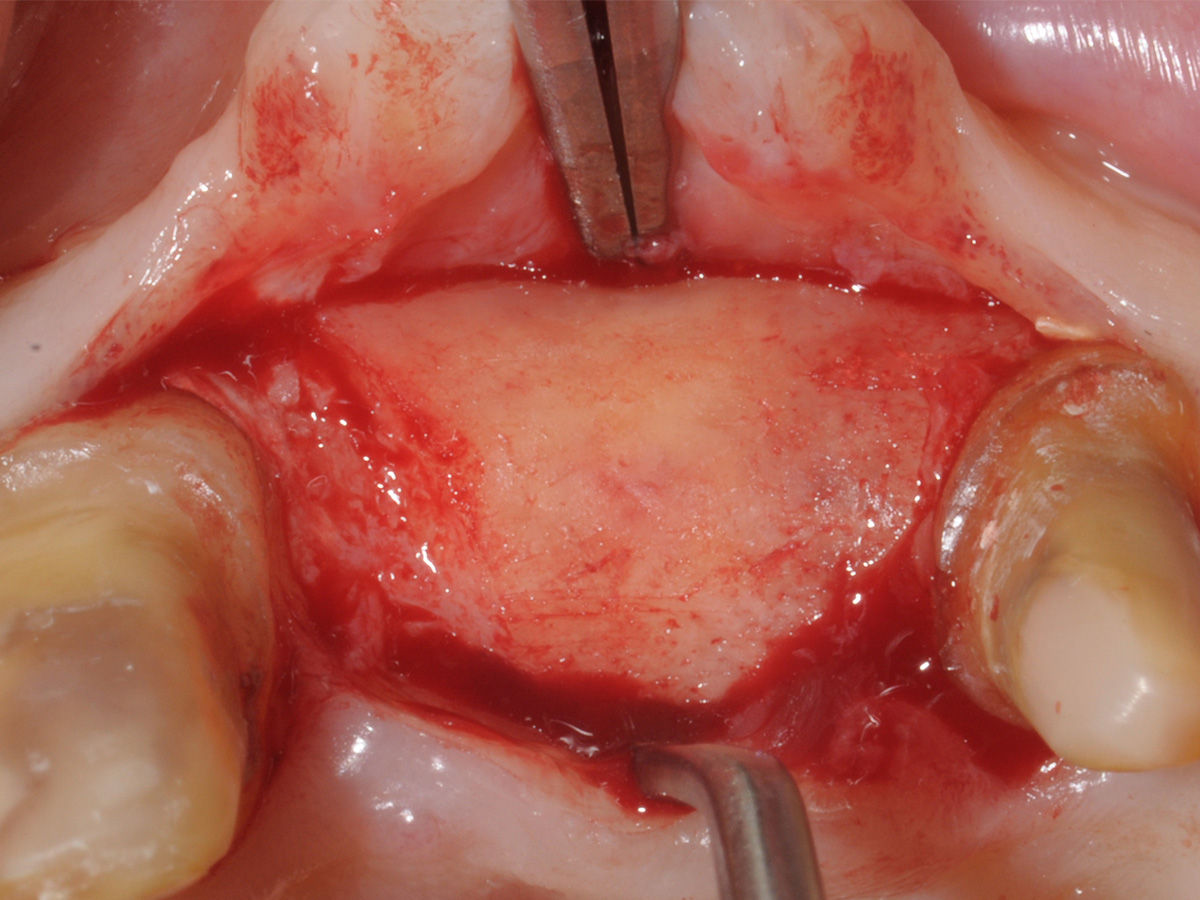

Dargestellter Defekt.

Abbildung 8

Aufbau mit OsteoBiol® mp3, Bone Lamina Soft und Evolution.